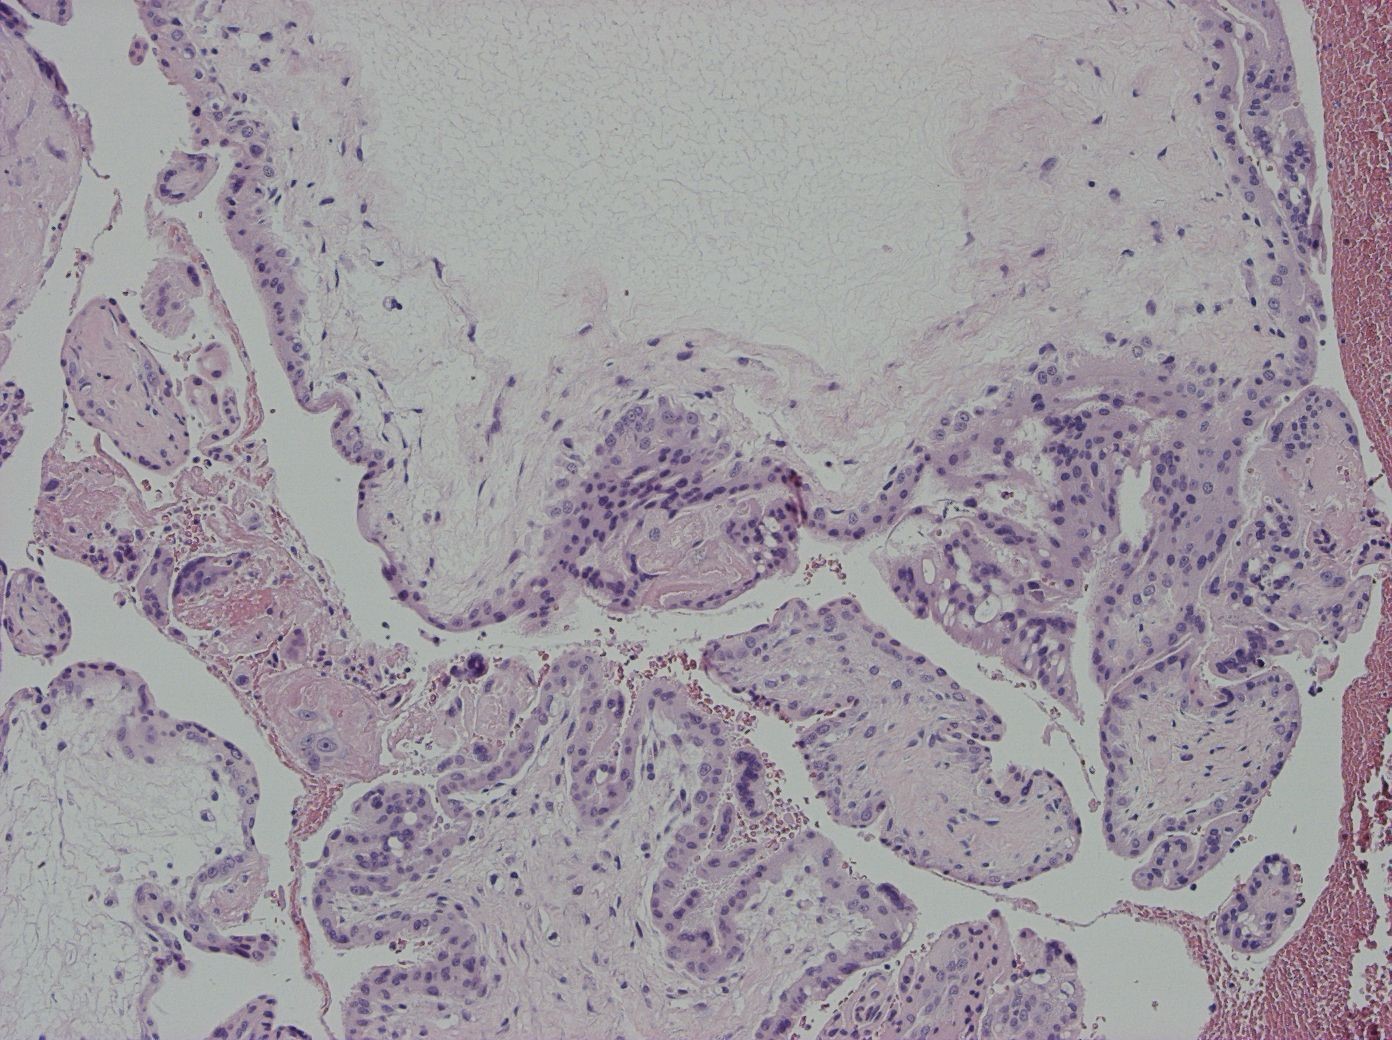

Partiell mola hydatidosa

Partiella molor är genetiskt triploida 138, med fokal hydatidiform omvandling av placentavilli. Spår av foster (såsom kärnförande erytrocyter) eller förekomst av fosterdelar kan ses, men fostret går oftast under i tidig graviditet. Vid partiella molor förekommer en fungerande villös cirkulation 139. Mikroskopiskt ses i typfallet två populationer av villi, med dels ödematöst förstorade villi med oregelbunden kontur, och dels små, ofta fibröst omvandlade villi. Inklusioner och cisterner kan förekomma. Trofoblasthyperplasin är generellt mindre uttalad jämfört med komplett mola.

Figur 8. Partiell mola HE.

Figur 9. Partiell mola p57KIP.